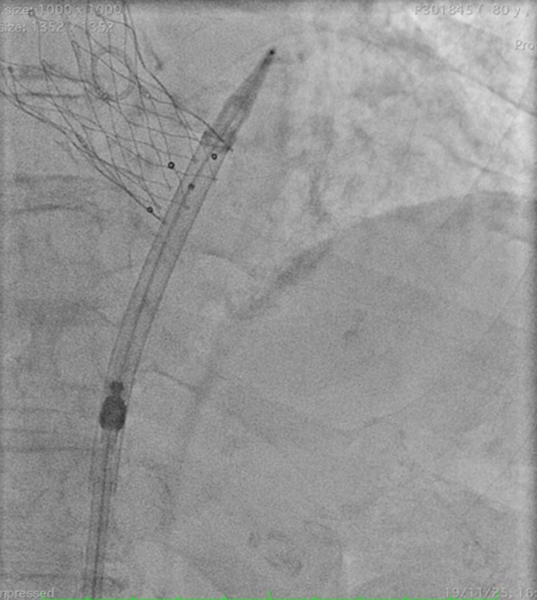

When the Safari wire is removed from the left ventricle by re-advancing the THV delivery system through the valve (Video 1), it may become entrapped due to a kinking within the THV catheter, preventing its removal (Figure 1).

Figure 1